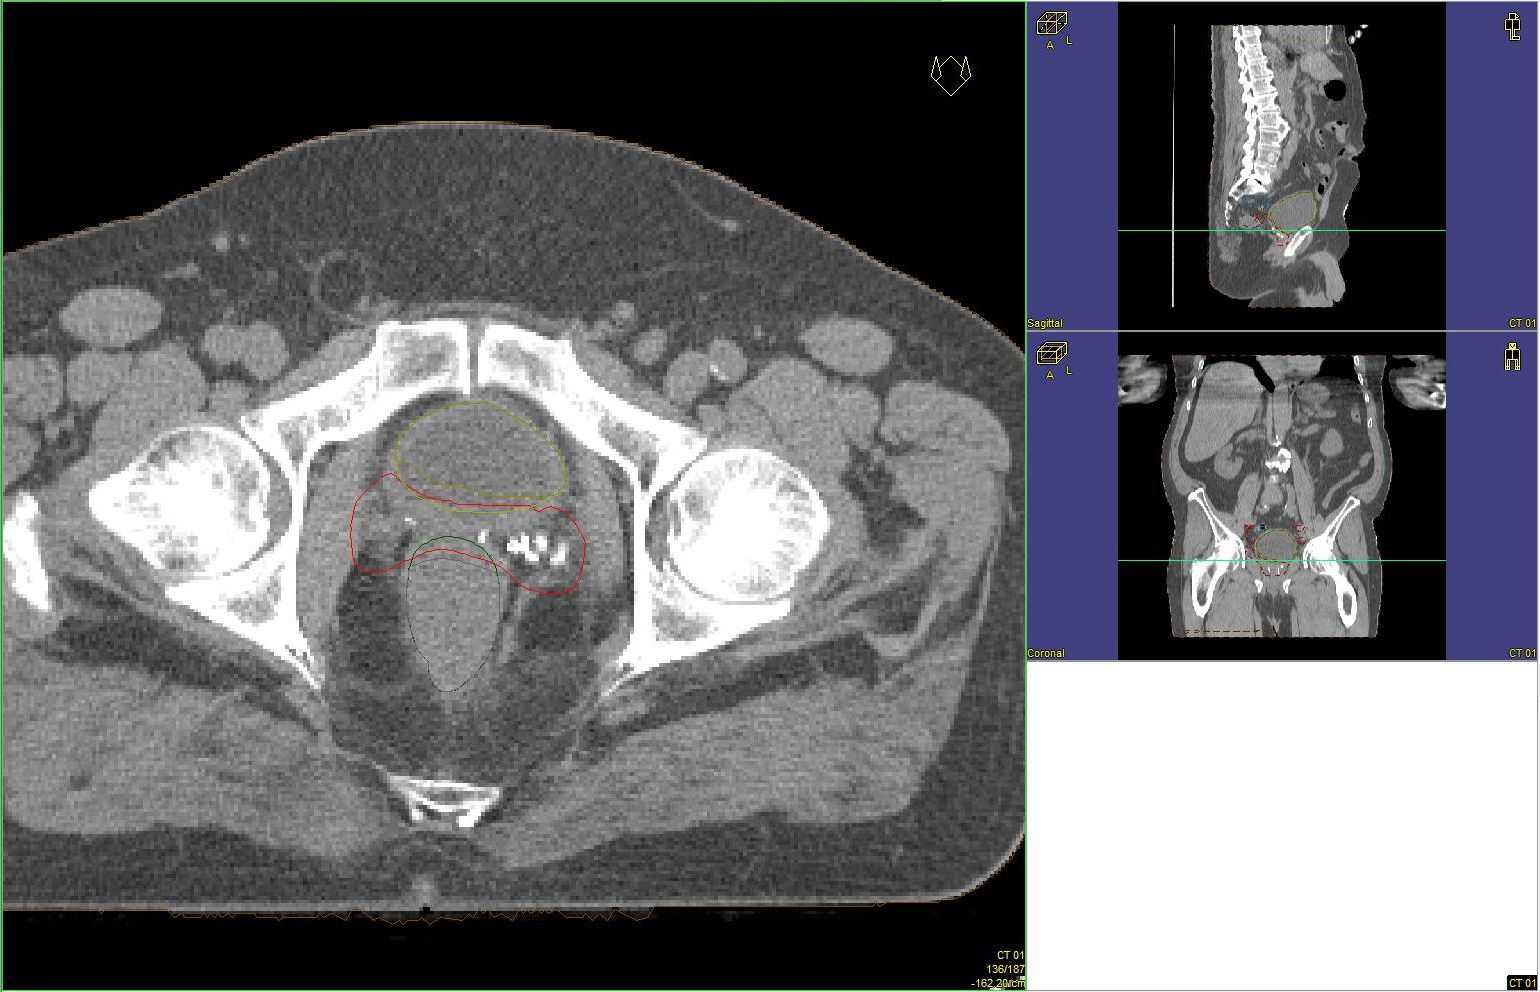

Prostata-Ca: Zielvolumen der postoperativen Radiotherapie

Beispiel: postoperative RT